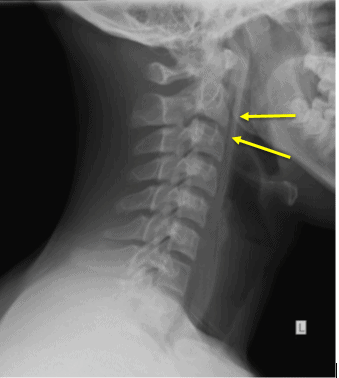

This patient was diagnosed with soft tissue emphysema, which can cause discomfort—what this patient perceived as a foreign body sensation. In this case it arose from pneumomediastinum tracking into the neck soft tissues (confirmed on the subsequently performed chest radiograph).

- Streaky hypodensities in the soft tissues of the neck compatible with gas

- This was like secondary to raised intrathoracic pressure from coughing after choking on food. Other possibilities for soft tissue emphysema include penetrating trauma and infection with a gas forming organism